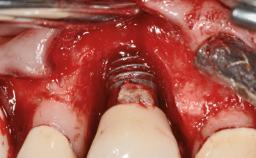

Peripheral Giant-cell Granuloma Associated with Peri-implant Tissues

Giant-cell granulomas (GCG) of the jaws are benign reactive lesions of unknown etiology, unrelated to giant-cell tumors (osteoclastomas), which are defined as benign but locally destructive and aggressive neoplasms (Jundt and coworkers 2005). Depending on their localization at the initial diagnosis, GCG are dived into central (CGCG) and peripheral (PGCG) types. CGCGs occur within the jawbones and appear as unilocular or multilocular radiolucent lesions. The incidence in the general population is very low. They are more commonly found in the mandible, mainly in children and young adults—patients are generally younger than 30 years—and have a greater incidence in females (Heithersay and coworkers 2002). The clinical behavior of CGCGs varies from slowly growing asymptomatic swellings to aggressive lesions that may result in pain, cortical perforation of the affected jaw site, and root resorption (de Lange and coworkers 2007).

Defining Characteristics More than three missing teeth to be replaced with an implant-borne prosthesis or prostheses

Placement Protocol Early or late implant placement